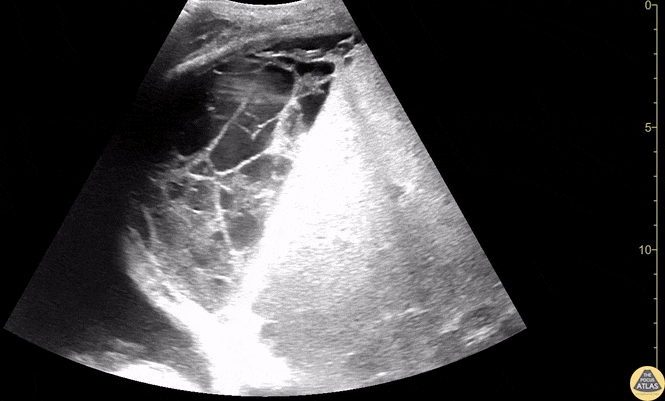

Biliary - Loculated Collection Within Liver

Located collection within the liver consistent with likely liver abscess. Contributors: Dimitri Livshits, DO; Jane Belyavskaya, MD; Chris Hanuscin, MD Kings County/SUNY Downstate